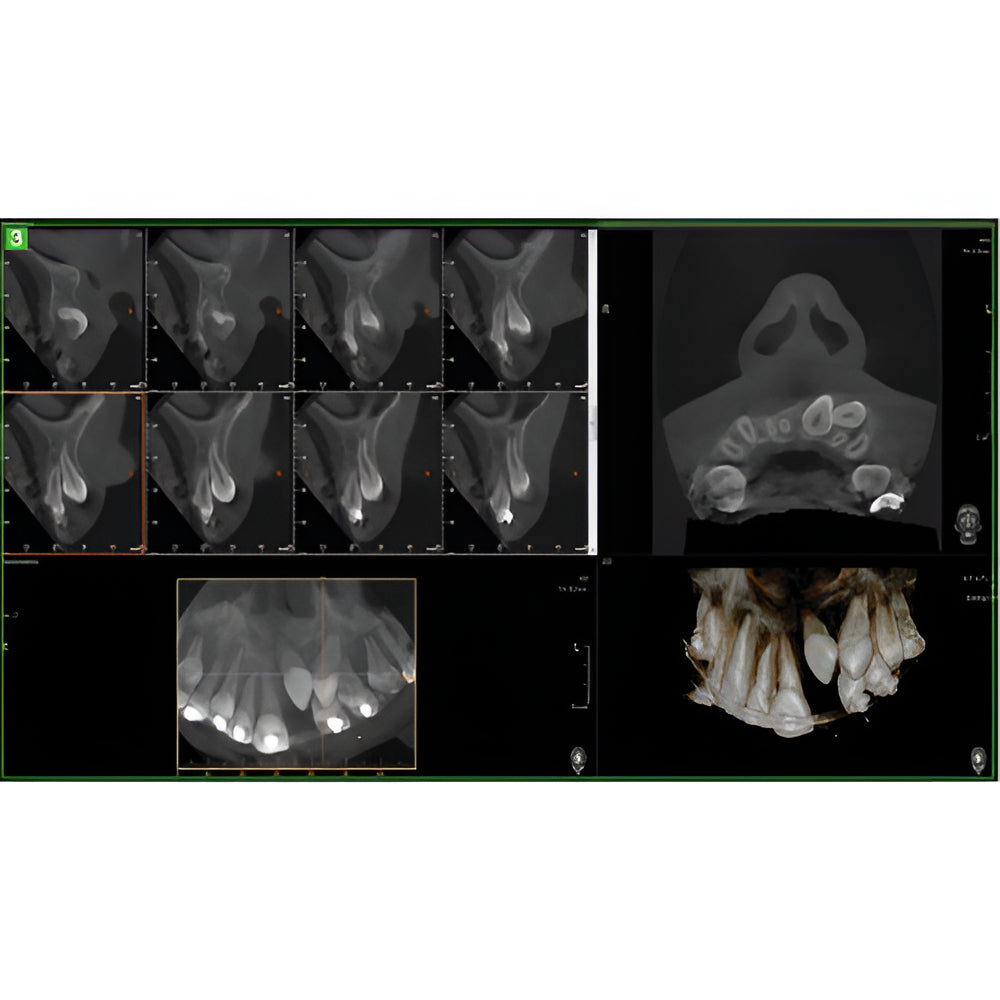

The Vatech PaX-i3D Green panoramic plus cone beam system delivers large field of view (up to 15 x 15 cm) dental CBCT scans in addition to standard 2D panorex and extraoral bitewing X-ray images. This Vatech CBCT machine features the innovative green CT technology which minimizes patient dose, while the Rapid Scan feature delivers high-quality 3D cone beam scans in just 5.9 seconds. A quick exposure time helps to minimize artifacts and motion, while at the same time reducing patient dose, making your imaging process more efficient and safer.

- EZ3Di Imaging Software with License

- 3D Cone Beam

- Multi-FOV

- Focused FOV

- Pedo Friendly